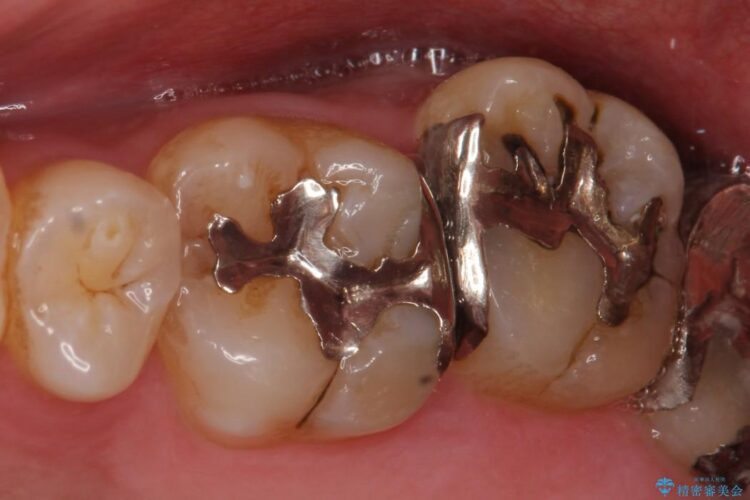

左上の他院で治療した銀歯の見た目が気になり白いものへ変えたいとの主訴で来院されました。

古い詰め物を外し、白く審美性の高いセラミックインレーにて再治療を行うこととしました。

今回は保険で治療してあった銀歯を審美性からセラミックインレーにて再度治療しました。

保険で治療した銀歯は、経年劣化で詰め物のふちが欠けたり、適合が悪くなり詰め物の下など目に見えない部分の虫歯の原因となることがあります。また、金属のため口にするものの熱の影響を受けやすく成分が溶けやすくなったり、変形してしまうことがあります。